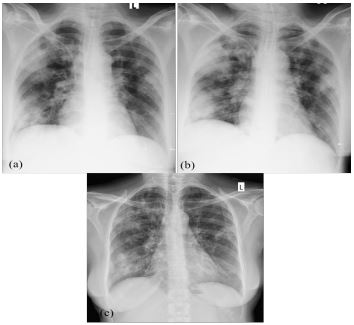

The arterial blood gas noted to have pH 7.154, PaO2 100.1 mmHg (FiO2 40%), PaCO2 35.8 (36-46) mmHg, HCO3 12.7 mmol/L (22-26) and lactate 7.5 mmol/L (0.5-1.6). Her capillary blood sugar was 566 mg/ dl and urinary ketone bodies found to be positive. The C-reactive protein was 290.05 mg/L and complete blood count had total white cell count of 6130 with neutrophil predominance. Her serum Sodium was 125 mmol/l. All other blood tests including liver and renal functions were unremarkable. The chest radiograph revealed extensive patchy consolidations in bilateral lung fields (Figure 1a).

Normal non-contrast Computed Tomography (CT) of the brain excluded intracerebral haemorrhage and cerebral infarction contributing to low GCS. Lumbar puncture and analysis of cerebrospinal fluid were deferred as patient had developed early bedsores. There was progression of chest radiographic abnormalities on repeat imaging (Figure 1b) even though the bronchial wash was sterile. There was no evidence of right side infective endocarditis on transthoracic echocardiogram. Human Immunodeficiency Virus testing was negative.

HSV-1 was detected in blood and bronchial wash by PCR while Cytomegalovirus (CMV) PCR was negative. Endobronchial biopsy confirmed acute inflammation and noted cytopathic features of intranuclear inclusions (Cowdry type A) (Figure 3). Intravenous acyclovir 500 mg 8 hourly administered from day 7 for HSV pneumonia and probable encephalitis. She started improving from the second day of acyclovir. She was extubated on day 5 of acyclovir treatment and she made a complete clinical recovery from her illness with marked improvement of imaging (Figure 1c). Intravenous acyclovir was continued for 2 weeks and discharged with oral acyclovir 400 mg 8 hourly for further 1 week after arranging follow up at Endocrinology clinic for diabetes mellitus.

Figure 1: Chest radiography. (a). On admission chest radiograph noted bilateral patchy consolidations more towards the peripheries (b). Progression of opacities (c). Chest radiograph taken 4 weeks after starting acyclovir-showing improvement.